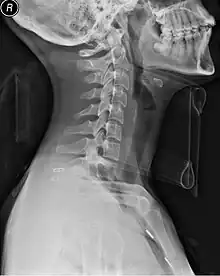

Collier cervical

Le collier cervical, ou minerve, également appelé collet cervical au Québec, est une attelle permettant d'immobiliser les vertèbres cervicales, c'est-à-dire le cou : il restreint les mouvements de la tête par rapport aux épaules. Il est généralement utilisé en cas de chute de hauteur et d'accident de la circulation, ou de trauma crânien et lorsque le choc a pu provoquer une lésion des cervicales.